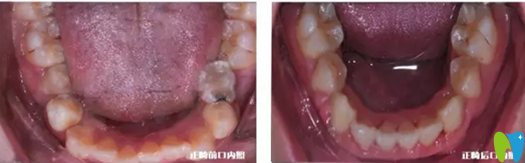

牙齒正畸前照片:

從上圖我們可以非常明顯的看出正畸前,小明的上牙有虎牙,而且上下牙咬合不健康,同時(shí)也很不美觀。

正畸前后牙齒對(duì)比照:

下牙正畸前后對(duì)比照:

通過這幾組對(duì)比圖,我們不難看出,小明的牙齒正畸效果不錯(cuò),上下頜達(dá)到良好磨合關(guān)系,中線也對(duì)齊了,上下頜咬合更加穩(wěn)定。